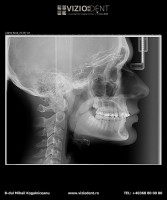

- teleradiografie laterală

- Pachet ortodontic: rx panoramic + teleradiografie laterală + fotografii intraorale şi extraorale + analiză computerizată a teleradiografiei laterale.